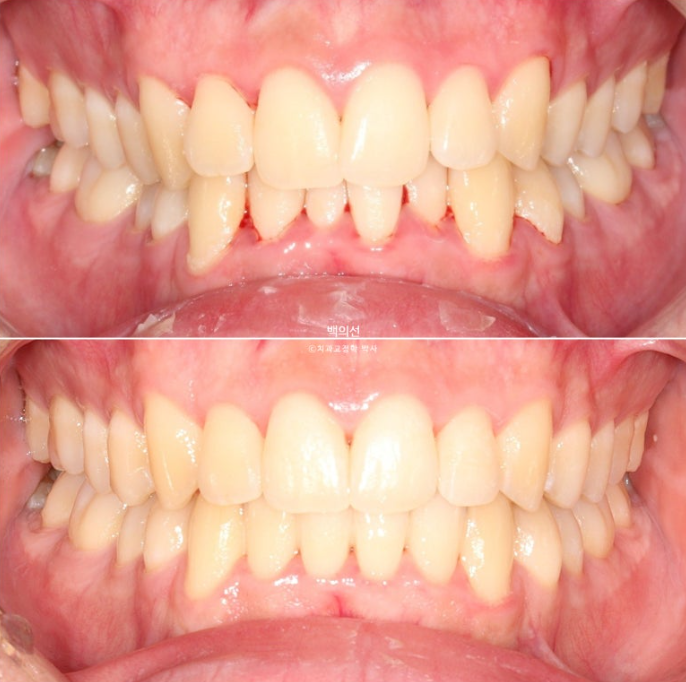

25.02~25.08

겨울방학에 들어와서 장치를 제작하고 학기동안 해외에서 치료를 이어간 뒤 여름방학에 다시 들어와 재제작 없이 5개월만에 마무리한 케이스를 보여드리겠습니다.

이제 전후 비교 보겠습니다.

토탈 치료기간은 3월부터 7월까지 5개월입니다.